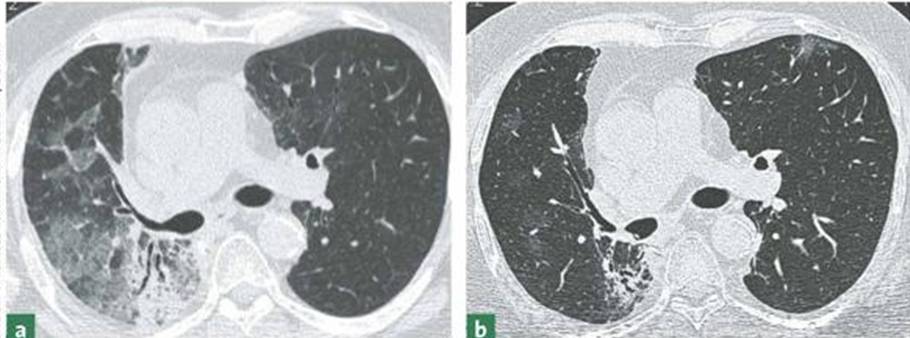

Bei der Strahlenbehandlung von Lungentumoren ist eine Exposition von normalem Lungengewebe meist nicht gänzlich zu vermeiden. Die dadurch hervorgerufenen Stress-Reaktionen führen zu akut entzündlichen Prozessen in der Lunge (Lungenentzündung), die jedoch wieder abheilen können. Allerdings können auch Schäden entstehen, die letztendlich die Elastizität der Lunge anhaltend beeinträchtigen und somit zu andauernden Atembeschwerden führen. Die Arbeitsgruppe am Institut für Toxikologie der Heinrich-Heine-Universität Düsseldorf untersucht, inwieweit eine Hemmung der oben genannten Rho Proteine – u.a. durch die als Lipidsenker weit verbreiteten Statine – dazu geeignet ist, die akuten und andauernden schädlichen Strahlenwirkungen auf das gesunde Gewebe der Lunge zu reduzieren. Auf diese Weise streben die Forscher eine wirksamere Tumortherapie bei gleichzeitig verminderten Nebenwirkungen an. Als Modell für diese Untersuchungen dienen Mäuse. Es wird überprüft, ob nach Bestrahlung des Brustkorbs der Tiere das Ausmaß toxischer Strahlenwirkungen auf die Lunge durch Gabe von Statinen verringert werden kann.